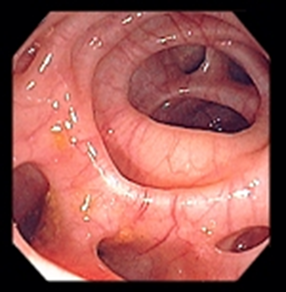

Kolon kanserinin dəqiqləşdiriliməsi üçün standart metod kolonoskopiya və biopsiyadır. Kolonoskopiya törəmənin yerini, sayını, ölçüsünü dəqiqləşdirə bilir və biopsiya etməyə imkan verir.

• Kolonoskopiyada kütlə

yob img 28  yob img 29